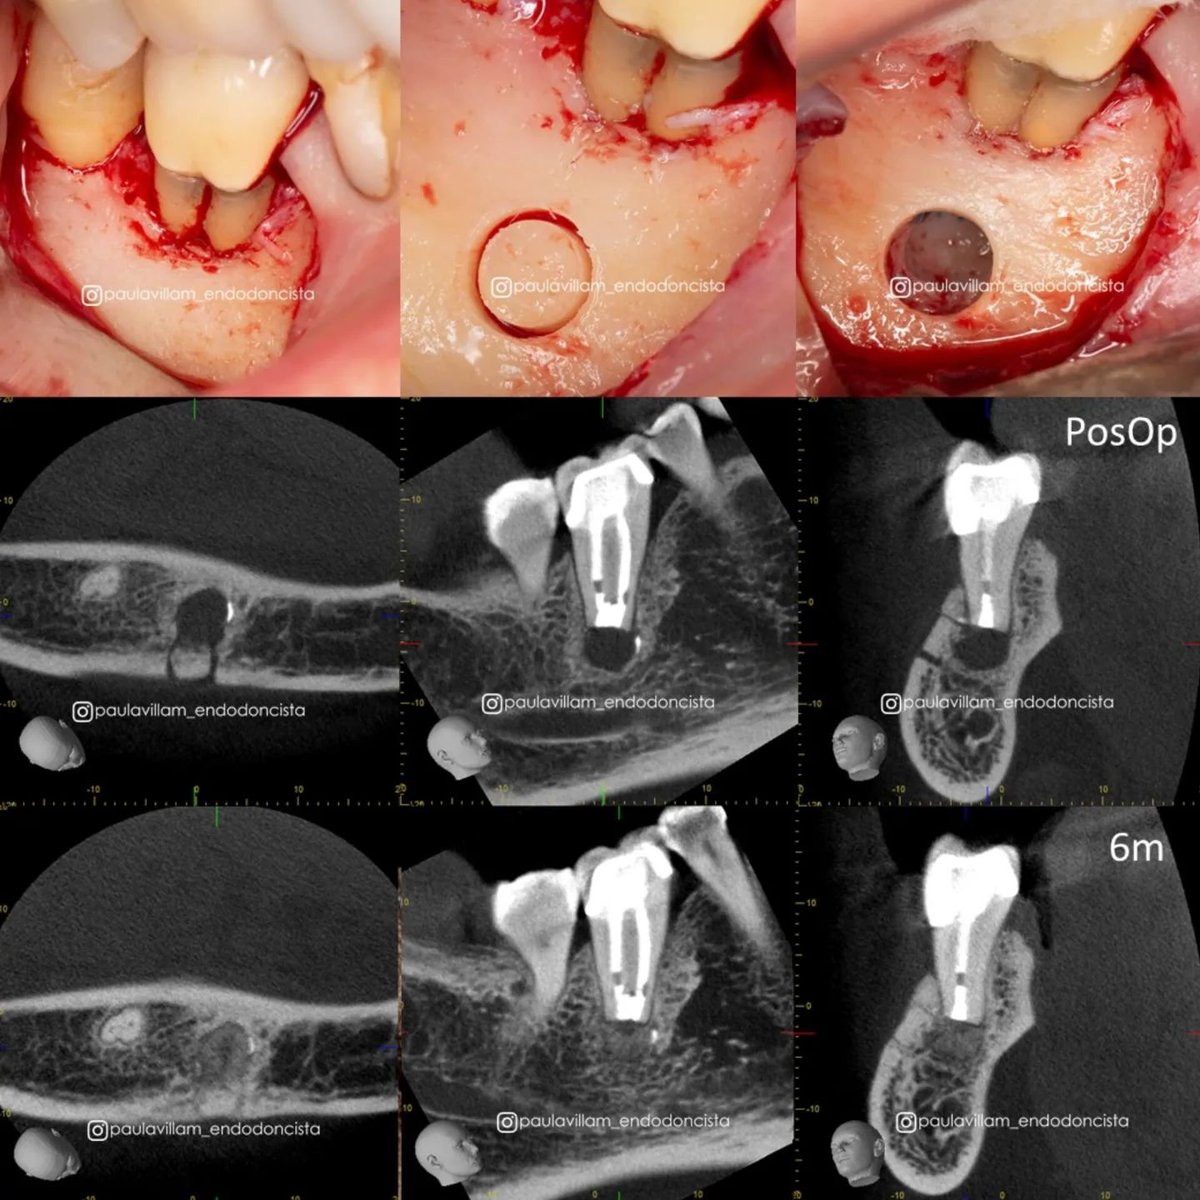

Second lower molar.

🎯Dynamically guided Endodontic MicroSurgery.

📐5mm round cortical window.

⏱️ 6months follow-up.😍

The pictures speak by themselves.

Case from Dr. Paula Villa